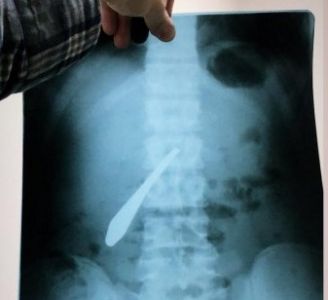

В ведомстве также пояснили, что мужчина обратился к врачам после того, как почувствовал острые боли в животе. Сделанный в больнице рентгеновский снимок показал застрявшую в кишке ложку. Причем, когда медики вытаскивали ее, то наткнулись в животе пациента на еще один столовый прибор.

«Вторая ложка была скрыта от рентгеновского снимка. Но повезло, что обе ложки находились в одном месте, что облегчило задачу хирургам», – говорится в сообщении Минздрава РД.